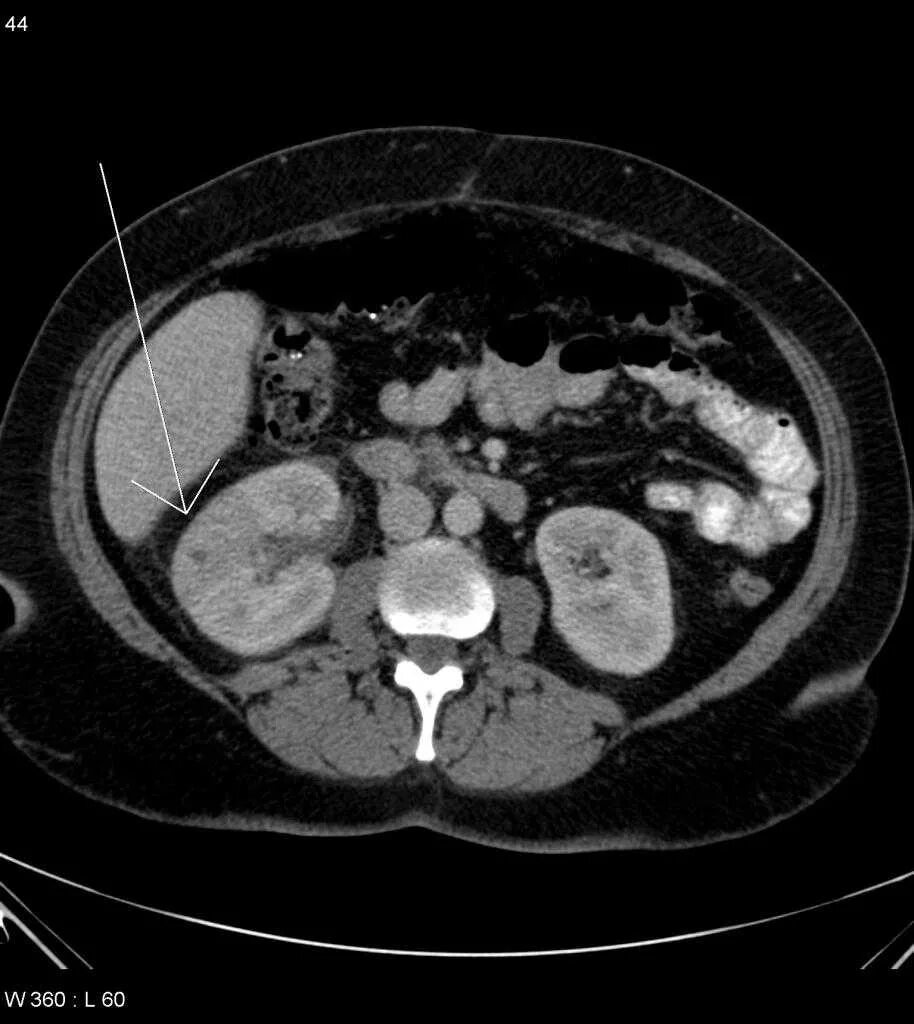

Пиелонефрит кт